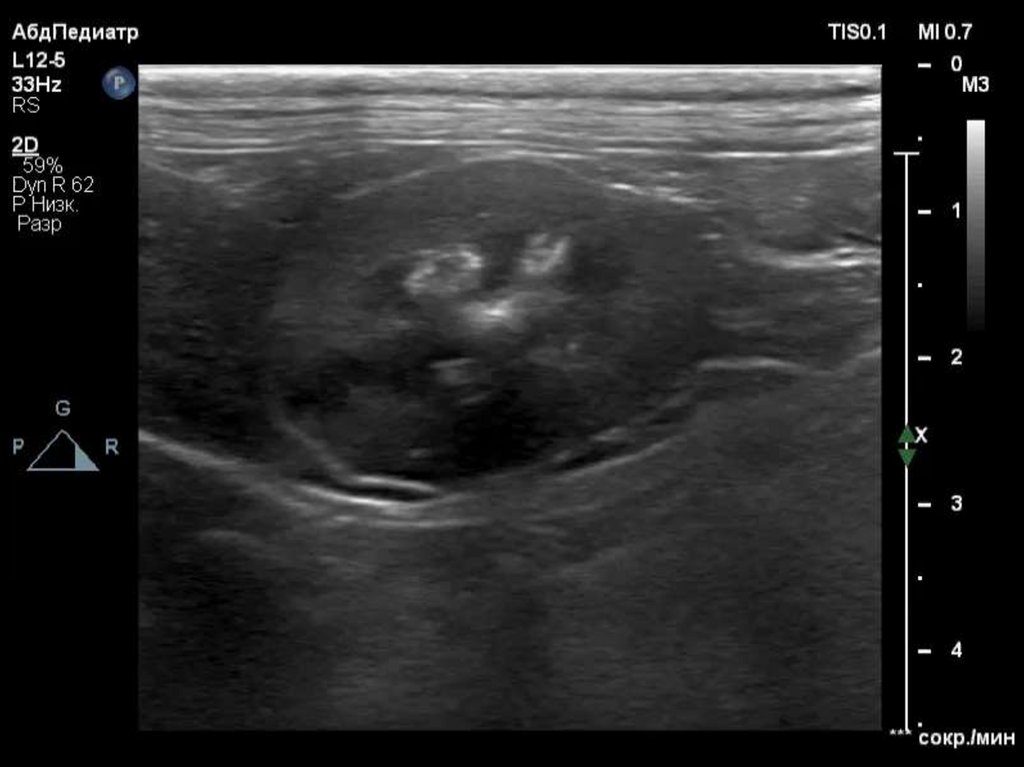

Неоплазия

• Многие опухоли продуцируют ПрПТГ и другие

компоненты, приводящие к гиперкальциемии (IL, TNFα,

TGF-a, кальцитриол).

• Метастазы в костную ткань могут усиливать резорбцию

костей.

• Распространенность гиперкальциемии при лимфоме у

собак 20%-40% (1), у кошек 30%-35% (2).

• Т-клеточная лимфома - наиболее распространенная

причина гиперкальциемии у собак (3)